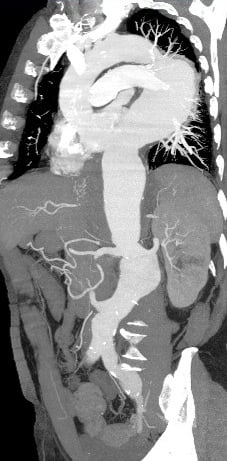

At CT scan control, 6 months after operation, the patient had a type-2 endoleak with enlargement of the aneurysmal sac.

CT-scan follow-up

- Complete type II endoleak resolution

- Absence of visceral ischemia

- No spinal cord ischemia